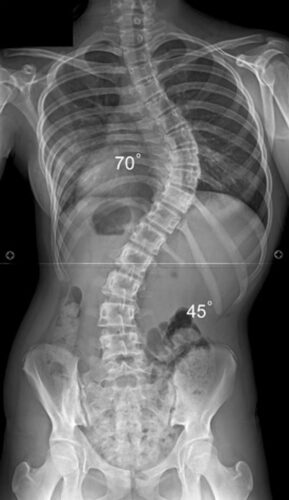

المريضة (أ): فتاة عمرها 16 عامًا مصابة بانحناء شديد (60 درجة)، تعاني من إمساك متكرر وتأخر في حركة الأمعاء.

الاعوجاج حالة مستمرة قد تحتاج تدخلًا في مراحل مختلفة من العمر. وبفضل وجود تقنيات التصنيف المعتمدة ، يمكن للأطباء تصميم خطة علاجية مخصصة تضمن تدخلاً جراحيًا عند الضرورة أو العلاج غير الجراحي قبل ذلك، لتفادي الاضطراب في الوظائف التنفسية أو أي أعراض متأخرة. فريقنا المحترف يضم نخبة من الأطباء والمتخصصين الذين يجمعون بين الخبرة والاحترافية لتقديم خطة علاجية شاملة ومخصصة لحالتك، تضمن السيطرة على الانحناء ومنع زيادته.